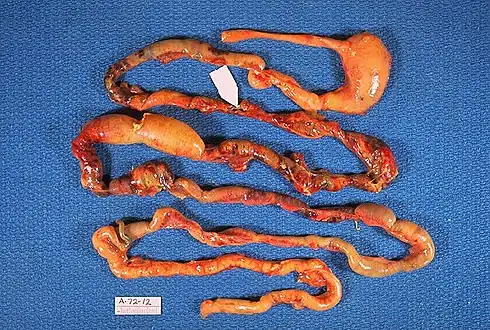

Alimentary tract of infant showing intestinal necrosis, pneumatosis intestinalis, and perforation site (arrow) (autopsy)

Alimentary tract of infant showing intestinal necrosis, pneumatosis intestinalis, and perforation site (arrow) (autopsy) Close-up of intestine of infant showing necrosis and pneumatosis intestinalis (autopsy)

Close-up of intestine of infant showing necrosis and pneumatosis intestinalis (autopsy)